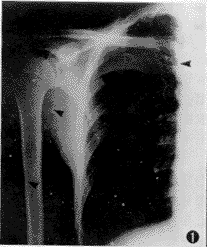

【摘要】 目的 比较在X线辅助下经外周静脉至中心静脉置管 (peripherally inserted central catheter, PICC) 与传统的经锁骨下静脉至中心静脉置管(central venous catheter, CVC)两种方法的优越性及并发症。方法 自1997年1月至1998年12月期间,在X线监视下,对PICC和CVC各60例病人进行临床研究,观察指标包括置管成功率、导管尖端的位置、并发症发生率。两组结果经显著性检验比较。 结果 经X线影像证实,PICC与CVC组一次穿刺置管成功率分别为95.0%(57/60例)和88.3%(53/60例),t=1.745, P=0.19;置管时间平均分别为13天(6~98 天)和14天(7~104 天) ,F=0.049, P=0.83;导管总阻塞率分别为6.7%(4/60例)和5.0%(3/60例),t=0.152, P=0.70;其中PICC组3Fr 型导管(20 G穿刺针)阻塞率(3/20例, 15.0%)高于4Fr 型导管(18 G穿刺针)(1/20例, 5.0%),t=1.111, P=0.29;导管尖端异位率分别为5.0% (3 /60例)和6.7%(4/60例),t=0.152, P=0.70,但PICC组经调整导管位置,并经X线影像证实,导管尖端均到达理想预定部位而继续使用;而CVC组异位导管均予以拔除。PICC组导管接头破裂1例(1.7%);外周静脉炎发生率为5.0%(3/60例) ......